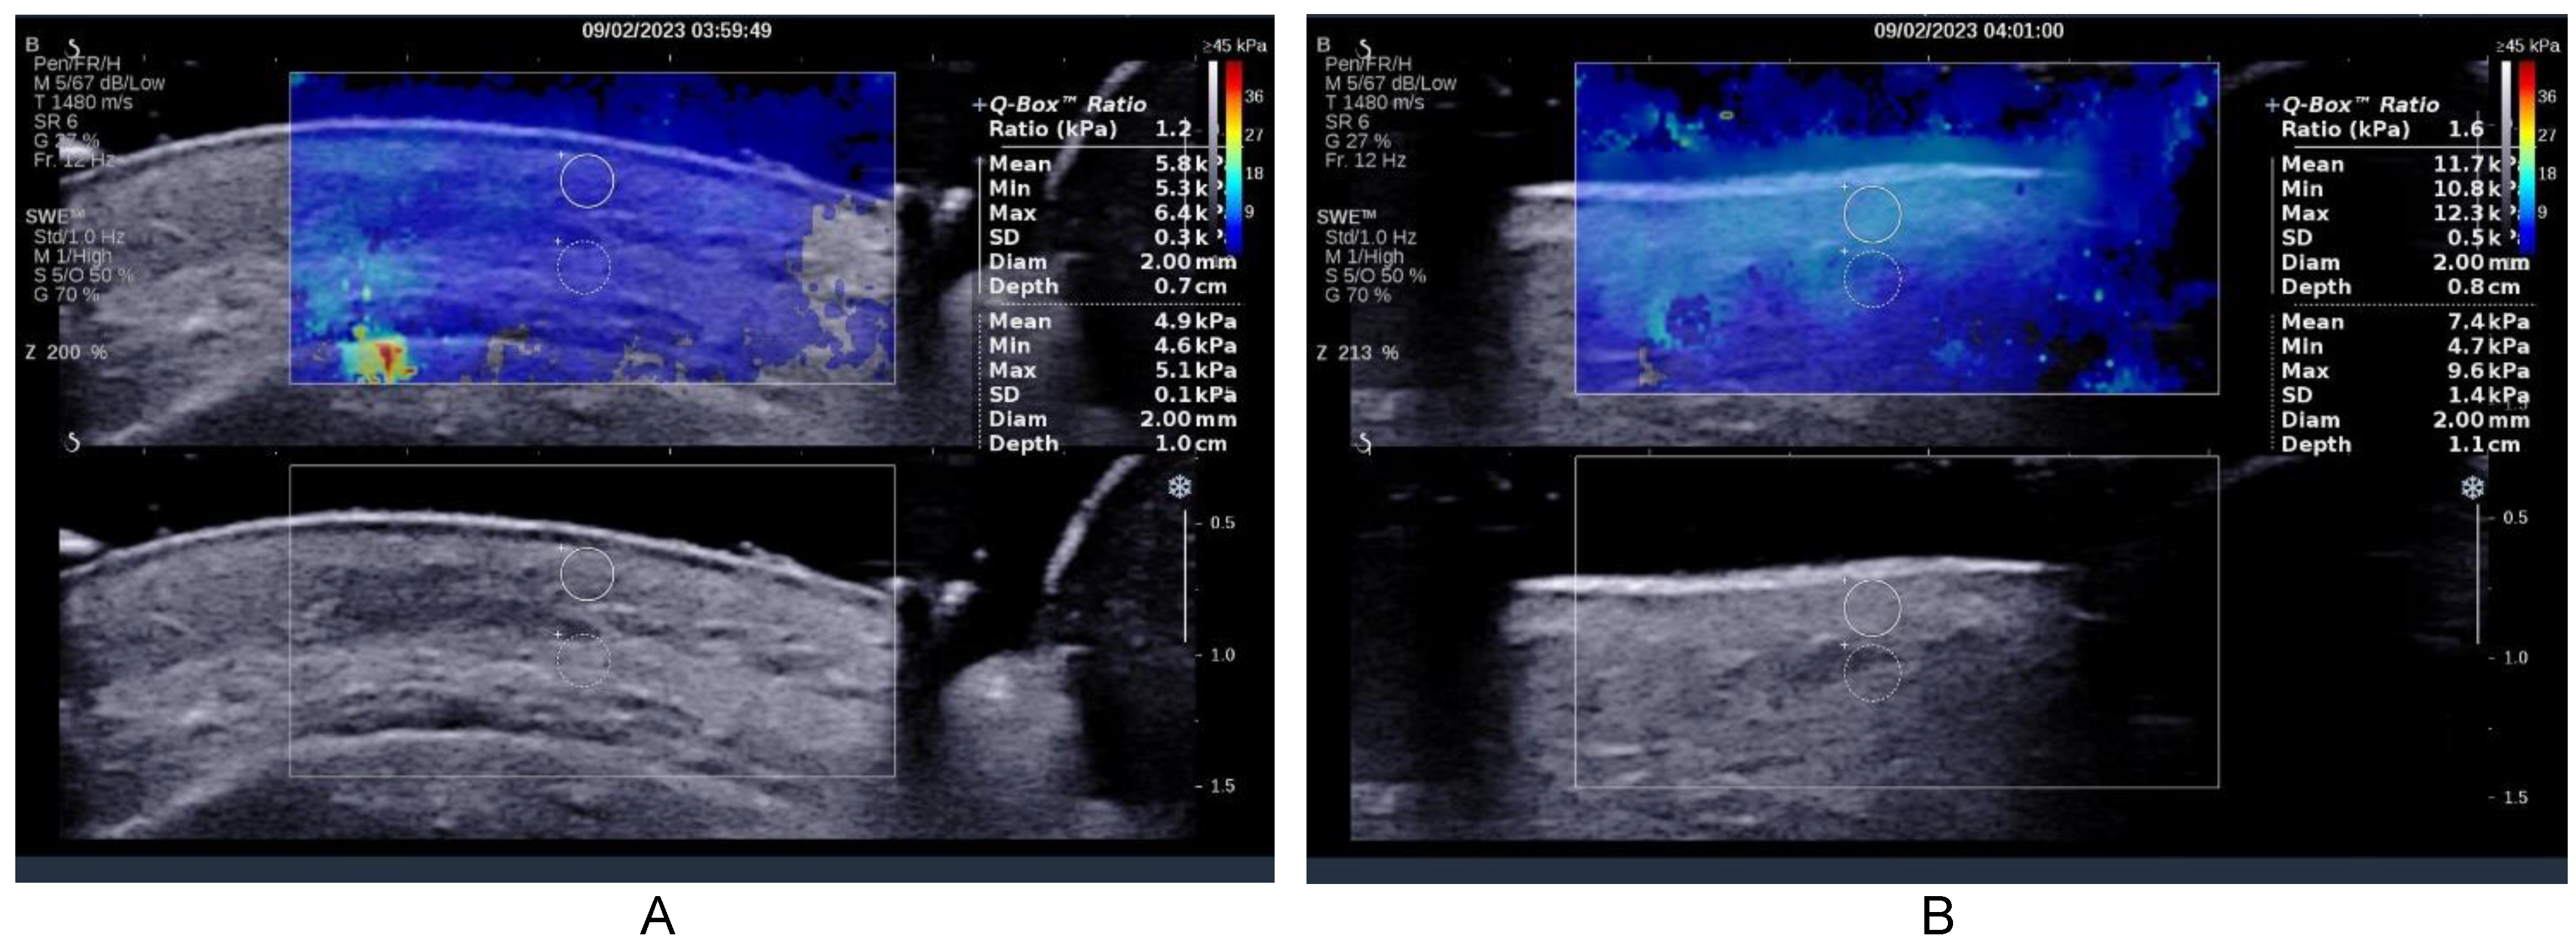

2.2. Ultrasound Examination